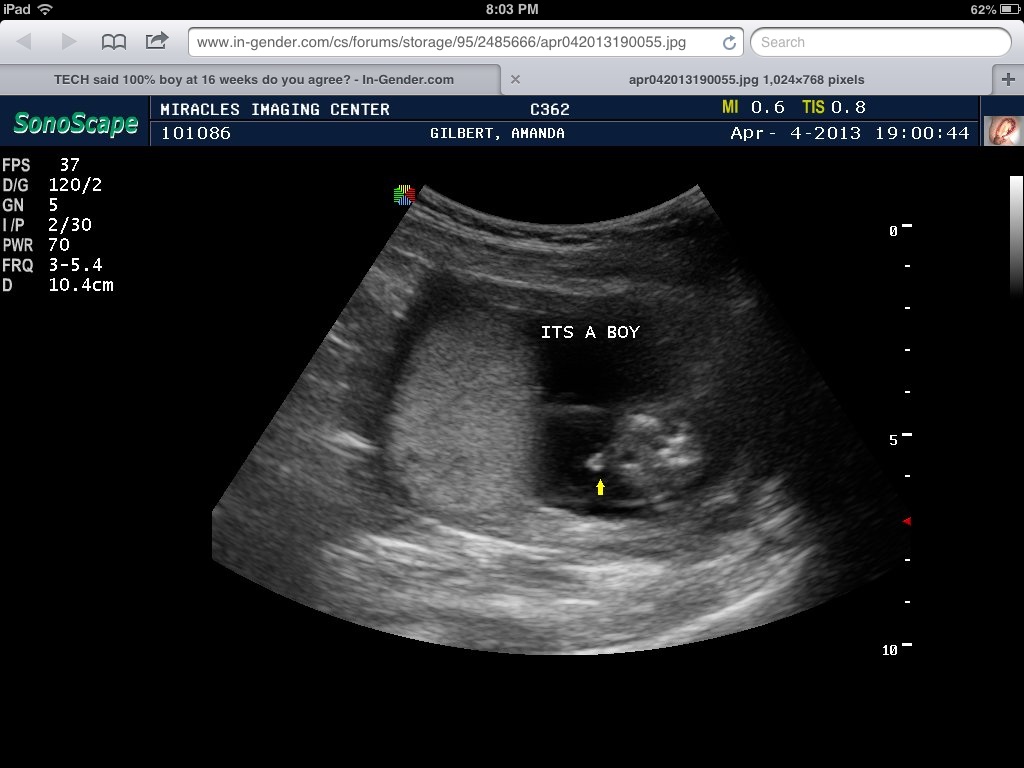

Can I buy blue? How certain are you?